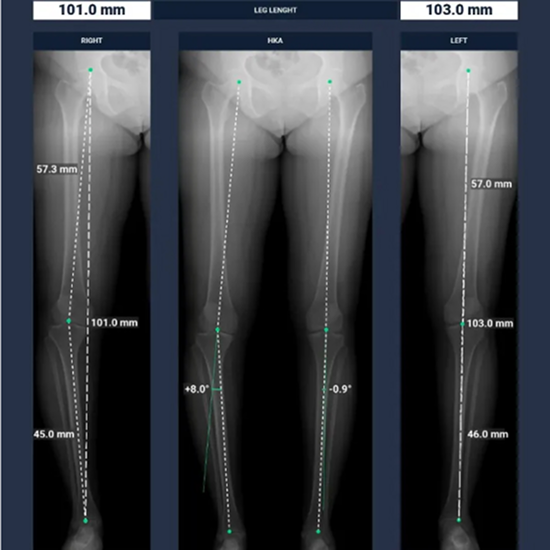

BoneMetrics automatically performs standard measurements for the feet, legs, pelvis/hips, and spine.

Through accurate point placement and easily understandable displays, the introduction of the software allows you to direct your attention to more critical tasks.

By introducing AI-supported standardization, variability can be reduced and reproducibility can be ensured.

Clinical studies prove that BoneMetrics matches the expertise of MSK radiologists, enabling your practice to provide the best possible service to patients.